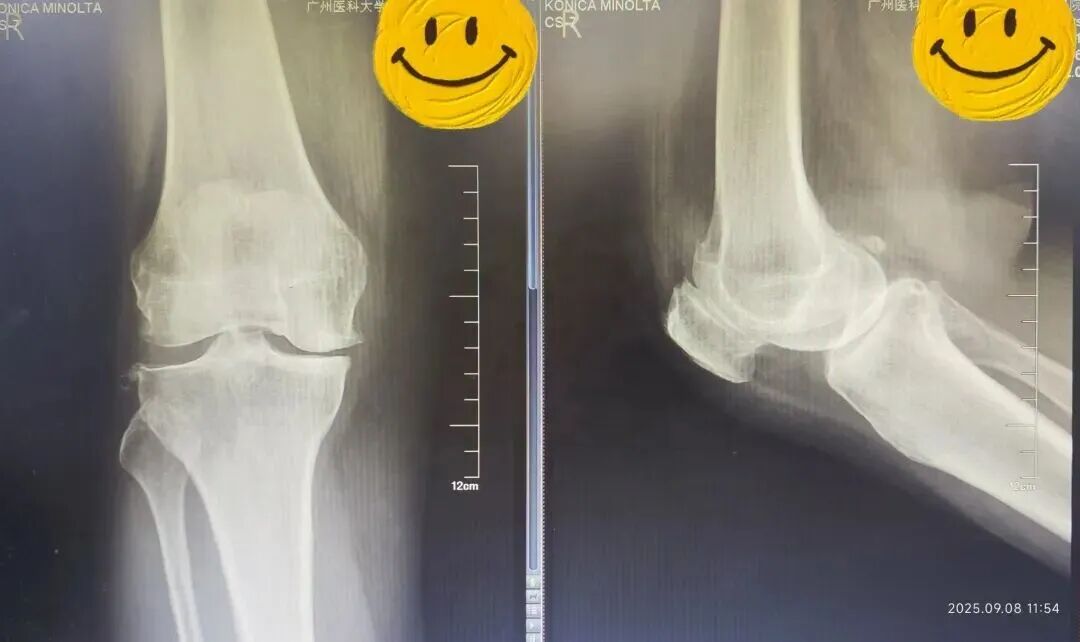

术前(左)术后(右)X线光片对比

接诊的骨科主任陈东峰发现,温女士左膝关节轻度肿胀,关节活动受限,有疼痛症状,结合影像学表现,符合膝关节退行性骨关节病的典型特征,建议她入院治疗。

在麻醉科配合下,陈东峰手术团队清除了增生的滑膜组织,去除了骨赘,对关节进行了适当松解,术中发现关节面磨损严重,软骨下骨暴露,内侧半月板后角脱位。医生精心安置了人工关节假体,替代了已经损坏的关节面。